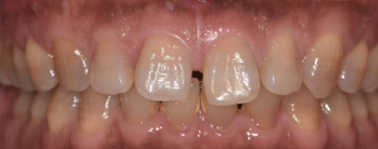

| 治療の経緯 | お母さまが子供の前歯の歯並びが気になるとのことで来院。 |

| 治療方法 | 右上2番が内側に入り込んでいる、部分的な反対咬合でしたので、 永久歯にだけ矯正装置をつけ、ワイヤーの力で、歯並びを改善しました。 |

| 治療期間 | 8ヵ月 |

|---|---|